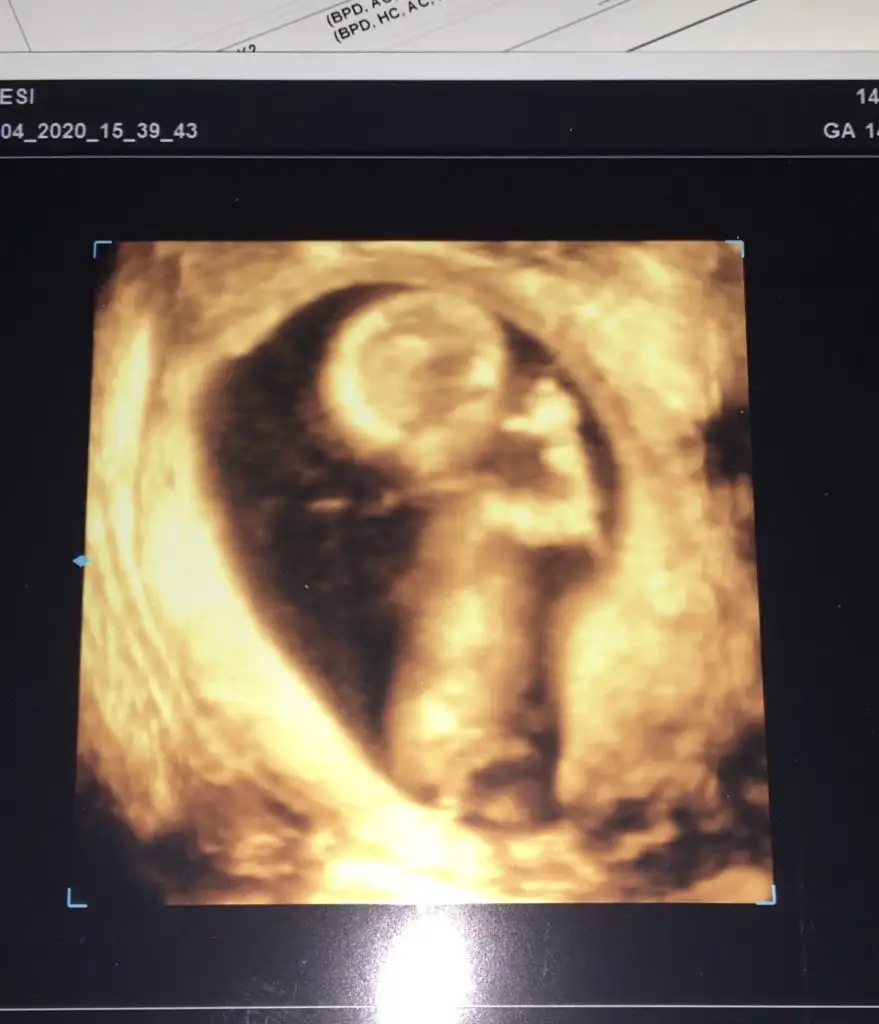

14 haftalık renkli ultrason var ama yine örttüKız yönünde12 olsa teyit ederim

Bi bakim onada14 haftalık renkli ultrason var ama yine örttü

oda buBi bakim onada

dr 100/80 kız dedi ikinci bu ilk kızımda 4 yaşında şuanNubu görünmüyor ama şekli şemali kız 10 haftalıkta kızilk bebekmi